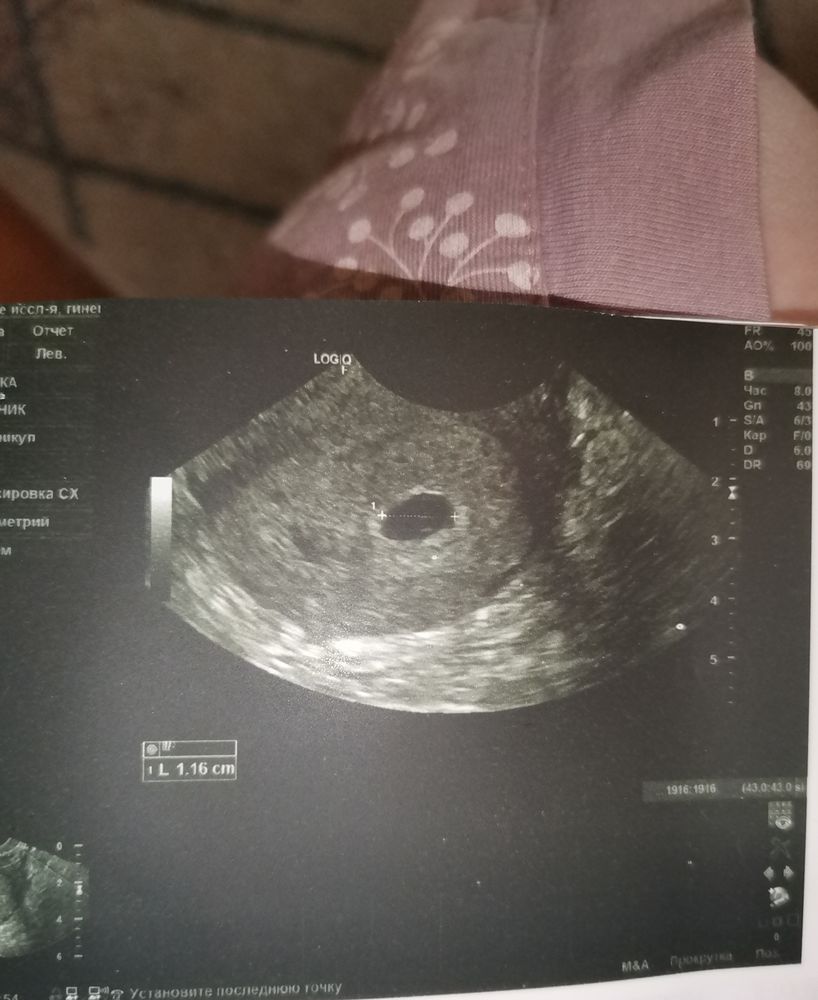

Второе узи 5 неделек 6 дней🥰

Всем приветик) Побывала вчера на УЗИ все хорошо растёт развивается😇Плодное яйцо с внутренним диаметром 11мм желточный мешочек 3мм) через 10 дней можно будет послушать сердечко😇главной причиной узи были ещё тянущие боли внизу живота. Слава богу отслоек нет, все ок только небольшой тонус. Сказали больше отдыхать))

Ну и фоточка с УЗИ на память🥰